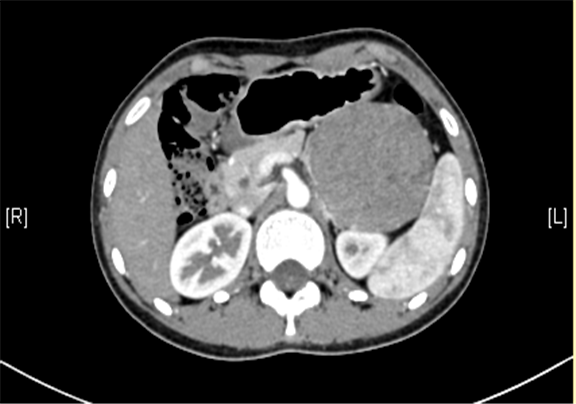

上腹部三维CT动态增强扫描: 胰腺体尾部类圆形软组织肿块,考虑实性假乳头状瘤可能性大。

模拟手术操作,自动计算肿瘤体积。肝脏体积为1018ml,肿瘤体积为229.7ml,肿瘤体积为肝脏体积的22.56%,13-14岁正常肝脏体积为1177.98±175.04ml,肿瘤来源于胰腺, 与脾较近,通过术前模拟手术,精准判断切除范围。

术前CT检查:

平衡期